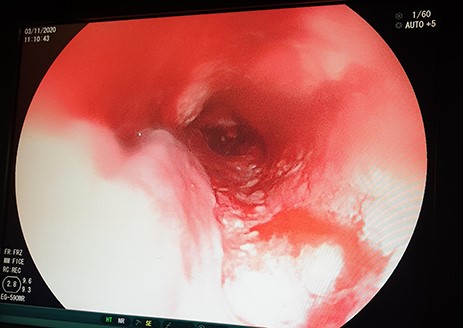

A 46-year-old female presented with progressive grade-six dysphagia, vomiting and significant unintentional weight loss. She was wasted and had a BP of 82/53 mmHg, pulse rate of 80 beats per minute, temperature of 36.4°C, saturating at 98% on room air. Her full blood picture was normal with haemoglobin of 12.3 g/dl, Creatinine 41 μmol/l, and urea was <1.0 mmol/l, sodium was 128.2 mmol/l, potassium 3.07 mmol/l. Chest X-ray was normal and the abdominal ultrasound showed no features of intra-abdominal metastasis. Oesophago-gastro-duodenoscopy (OGD) revealed a fungating tumour at 20 cm with almost complete obstruction (Fig. 1) and biopsies taken revealed oesophageal well differentiated invasive squamous cell carcinoma.

OGD showing a fungating tumour at 20 cm from the upper incisors with almost complete luminal obstruction.